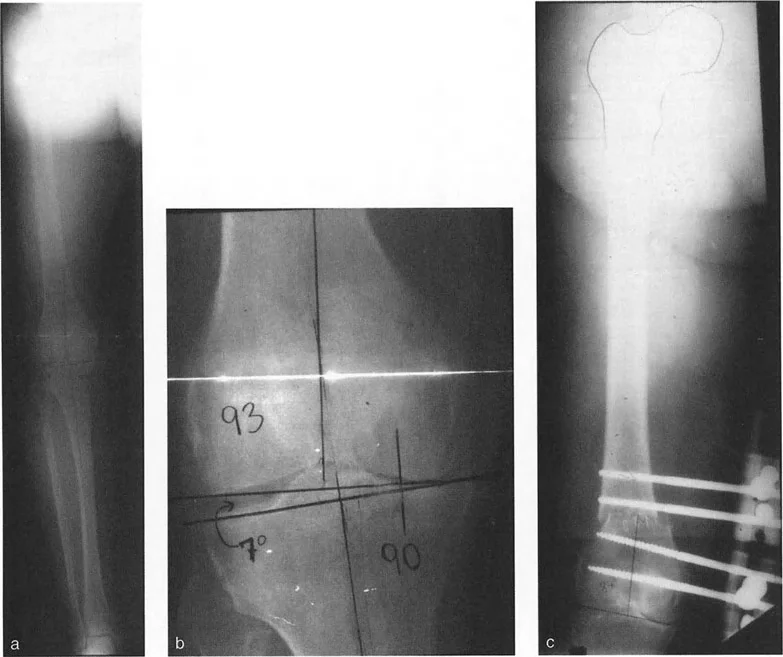

لفهم تطبيق قطع العظم القبة المحورية، سنتناول مثالاً رئيسياً: تصحيح تشوه الفحج (Valgus Deformity) في الفخذ البعيد باستخدام تقنية التثبيت بمساعدة المثبت الخارجي (Fixator-Assisted Nailing - FAN). هذه التقنية هي فلسفة هجينة تجمع بين دقة التثبيت الخارجي وراحة المسمار النخاعي الداخلي.

تستخدم تقنية FAN مثبت خارجي مؤقتاً أثناء الجراحة لتحقيق تثبيت مثالي وصلب للمحاذاة. بمجرد استعادة المحور الميكانيكي بدقة بواسطة المثبت الخارجي، يتم إدخال مسمار نخاعي لتأمين التصحيح بشكل دائم، مما يسمح بإزالة المثبت الخارجي في نهاية العملية. هذا يوفر للمريض دقة إطار إليزاروف دون العبء النفسي والجسدي لارتدائه لأشهر.

الخطوة 1: التخطيط قبل الجراحة وتحديد CORA

يبدأ كل شيء بالتخطيط الدقيق. لنفترض مريضاً يعاني من تشوه فحج شديد في الفخذ البعيد (على سبيل المثال، 13 درجة فحج)، مع تحديد مركز دوران الانحراف (CORA) عند مستوى خط المفصل.

توضح الصورة التخطيط قبل الجراحة لتصحيح تشوه الفحج في الفخذ البعيد، مع تحديد مركز دوران الانحراف (CORA) عند مستوى خط المفصل.

نظراً لأن CORA يقع عند خط المفصل، لا يمكن إجراء قطع العظم بالضبط عند CORA بأمان (وفقاً لقاعدة بالي الأولى). لذلك، يجب إجراء قطع العظم بشكل أقرب إلى CORA ولكن ليس عليه بالضبط (قاعدة بالي الثانية). تتطلب القاعدة الثانية أنه إذا تم قطع العظم على مستوى مختلف عن CORA، يجب ألا يتم تغيير الزاوية فقط، بل يجب أيضاً إزاحة نهايتي العظم (ترجمة) لاستعادة المحور الميكانيكي بالكامل دون إنشاء تشوه إزاحة ثانوي.